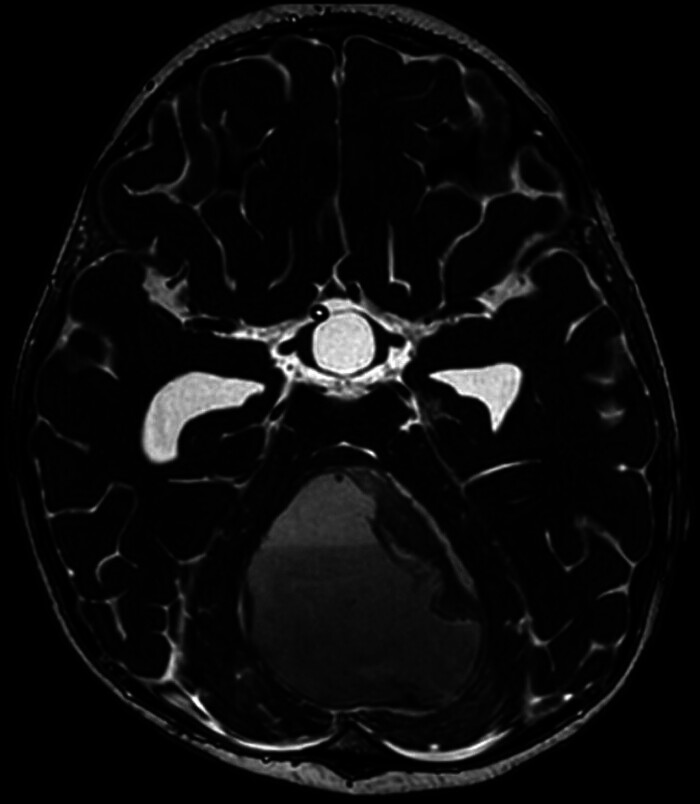

一名2岁的女性患者在经历了全身性强直阵挛性发作并伴有发热后出现意识丧失。她接受了紧急右额部外脑室引流术。术中脑脊液分析感染模式阴性。MRI显示后窝中线主要为囊性病变,伴压缩肿块效应。随后,她接受了枕下开颅术,显微切除后颅窝病变。组织病理学报告角蛋白薄片伴严重活动性炎症,异物型巨细胞反应,头皮切除游离毛轴穿过炎症灶,与毛突窦一致。病人随后健康出院回家。

A 2-year-old female patient presented after experiencing a generalized tonic-clonic seizure accompanied by fever, followed by a loss of consciousness. She underwent an urgent right frontal external ventricular drain placement. Intraoperative cerebrospinal fluid analysis was negative for infectious patterns. MRI showed a predominantly cystic lesion in the midline posterior fossa, with a compressive mass effect. Subsequently, she underwent a suboccipital craniotomy for microscopic resection of a posterior cranial fossa lesion. Histopathology reported keratin flakes with severe active inflammation, and foreign body type giant cell reaction in scalp excision with free hair shafts through the inflammatory focus, consistent with pilonidal sinus. The patient was then discharged home in good health.